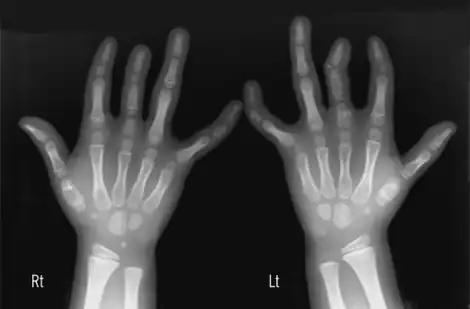

Brachydactyly (Greek βραχύς = "short" plus δάκτυλος = "finger"), is a medical term which literally means "short finger". The shortness is relative to the length of other long bones and other parts of the body. Brachydactyly is an inherited, usually dominant trait. It most often occurs as an isolated dysmelia, but can also occur with other anomalies as part of many congenital syndromes. Brachydactyly can also be a signal that one will be at risk for heart problems as they age.